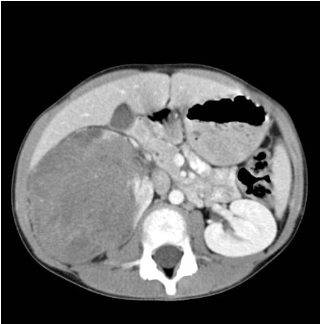

A 35-year-old male presents to the office with bilateral abdominal pain and hematuria, progressing during the past 2 months. He states that the pain is located over his flank and is relatively unchanged based on position or time of the day. He has not taken any over-the-counter medications, but heating pads provided no relief. Vital signs reveal a blood pressure of 150/90 mmHg. Physical and osteopathic examination reveals abdominal fullness, with maximal tenderness to palpation at the level of T10 and a discrete somatic dysfunction at that level. Costovertebral angle tenderness is mildly present bilaterally. An abdominal CT scan is obtained as shown in the exhibit. The patient states that his father also had "cysts on his kidneys" but passed away suddenly at 42 years of age.

Which of the following is true regarding this person's disease state?